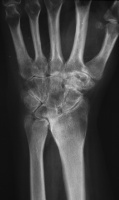

| She had progressive deterioration over two years with worsening pain and instability. |

| Opposite side, asymptomatic: |